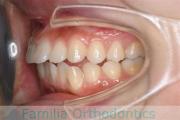

でこぼこと口元が出ている横顔が気になるとのことで来院されました。重度の叢生(ガタガタ)と側方へのズレがあるため、アンカースクリューを併用したマルチブラケット法にて治療を行いました。3年弱、35回程度の通院をしていただきました。叢生が強いため、部分的にガタガタが再発・後戻りするリスクが高いケースでした。

- ≫治療前

-

上顎

下顎

前歯の関係など

右側

正面

左側